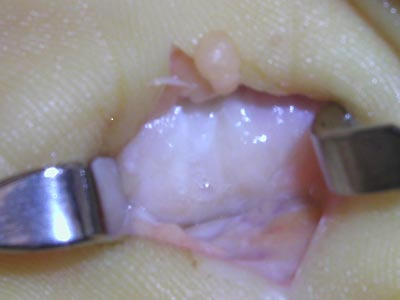

Stenozan tenosinovit olarak da adlandırılan tetik parmak, parmaklarda veya başparmakta görülen, ağrılı bir durumdur. Parmaklara yumruk yaptıran fleksör tendonlar, tendonların sürtünme olmadan kaymasını sağlayan ve tenosinovium denilen bir kılıfla kaplıdır. Tendonlar seyirleri boyunca elde belirli bölgelerde pulley denen kemerlerin altından geçerler. Bu kemerler tendonları yerinde tutar. Tendon genişliğinin artması ya da pulleyin kalınlaşması hareketli tendon üzerinde sürtünmeye neden olur. Tetik parmak hastalığında, bu durum tendonun ileri geri hareket etmesini zorlaştırır.

A.Tendon genişliği artmış ya da B.Pulley kalınlaşmıştır.

Bu nedenle parmak hareketi zor ve ağrılı hale gelir. Bu olay ilerler ise parmak belli bir pozisyonda kilitlenip kalır, zorlayınca tetik gibi atmaya başlar. En sık etkilenen parmaklar yüzük parmağı ve başparmaktır, ancak bu durum herhangi bir parmağı etkileyebilir.